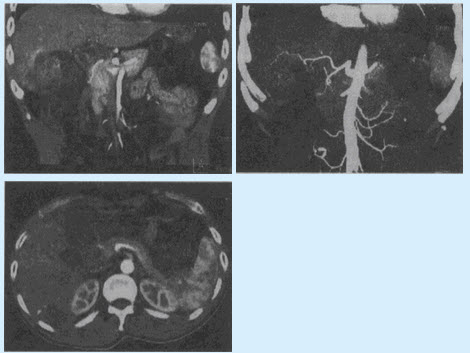

患者,男,43岁。体检发现左肾上腺肿物4天。患者4天前B超发现左中上腹肿物,边界尚清,形态欠规则,不伴头痛、头晕,不伴心悸、视物模糊。查体:BP111/66mmHg。

(单选题)CT检查如下图,拟诊断()

A:肾上腺增生

B:肾上腺腺瘤

C:肾上腺结核

D:肾上腺嗜铬细胞瘤

E:肾上腺脓肿

F:肾上腺囊肿

第2题,共3个问题

(多选题)该病表现正确的是()

A:阵发性高血压、头痛、心悸、多汗

B:肾上腺皮质是肿瘤发生的主要部位

C:实验室检查24小时儿茶酚胺代谢物明显高于正常

D:老年人易发病

E:10%发生在肾外

F:易发生异位改变

第3题,共3个问题

(单选题)该病最适合的检查方法是()

A:CEA

B:MRA

C:MRI

D:CT

E:B超

F:DSA